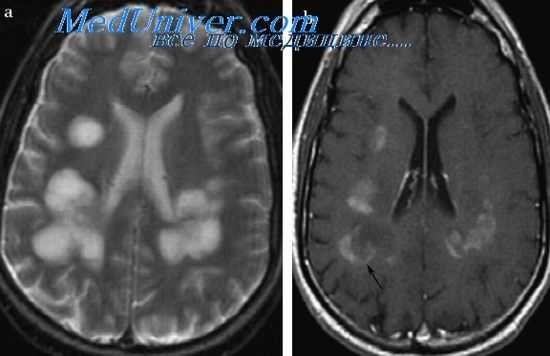

Радиографические методы исследования (КТ и МРТ) выявляют значительные очаги поражения в области базальных ганглиев, таламуса и ствола мозга.